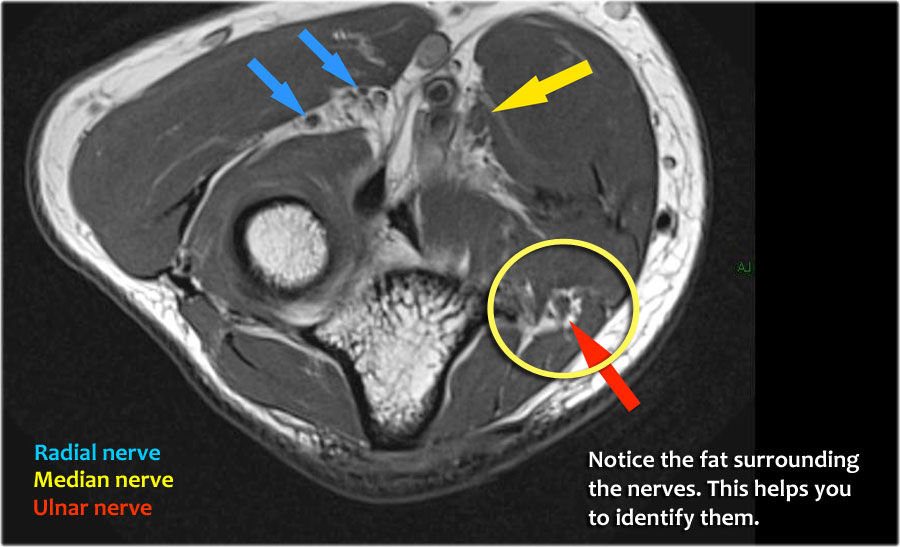

Nerves

Scroll through the images.

Radial nerve

Dây thần kinh quay có thể được xác định rõ nhất ở mức chỏm xương quay, nơi có thể quan sát thấy các nhánh nông và nhánh sâu trong ống xương quay (mũi tên).

This is a very consistent place to find the radial nerve.